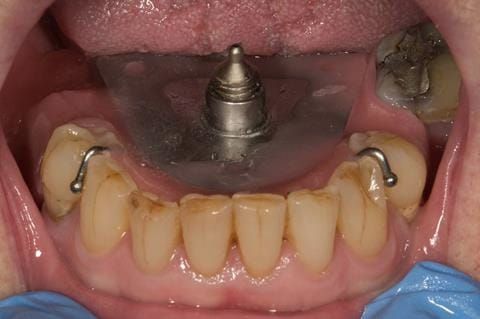

Following consultation and second discussion appointment the patient chose to have option 2 namely, a window denture - maxillary cobalt chromium based partial denture. The clinical situation and treatment process is shown in detail below with photographs. The patient was successfully rehabilitated with this and her quality of life considerably improved. The clinical work was provided by Finlay and the technical work by Rowan.